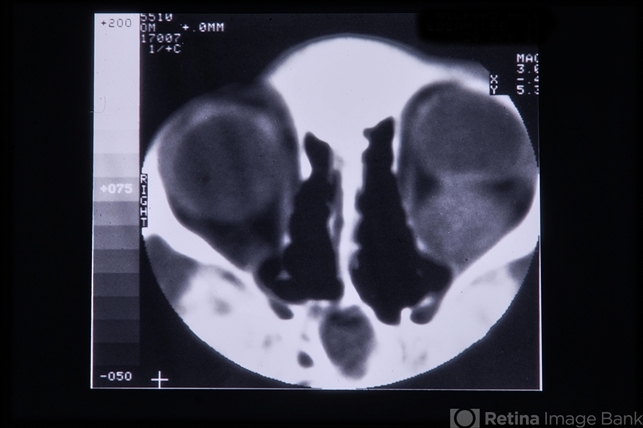

- Rhabdomyosarcoma

- rhabdomyosarcoma, CT scan

- CT scan.